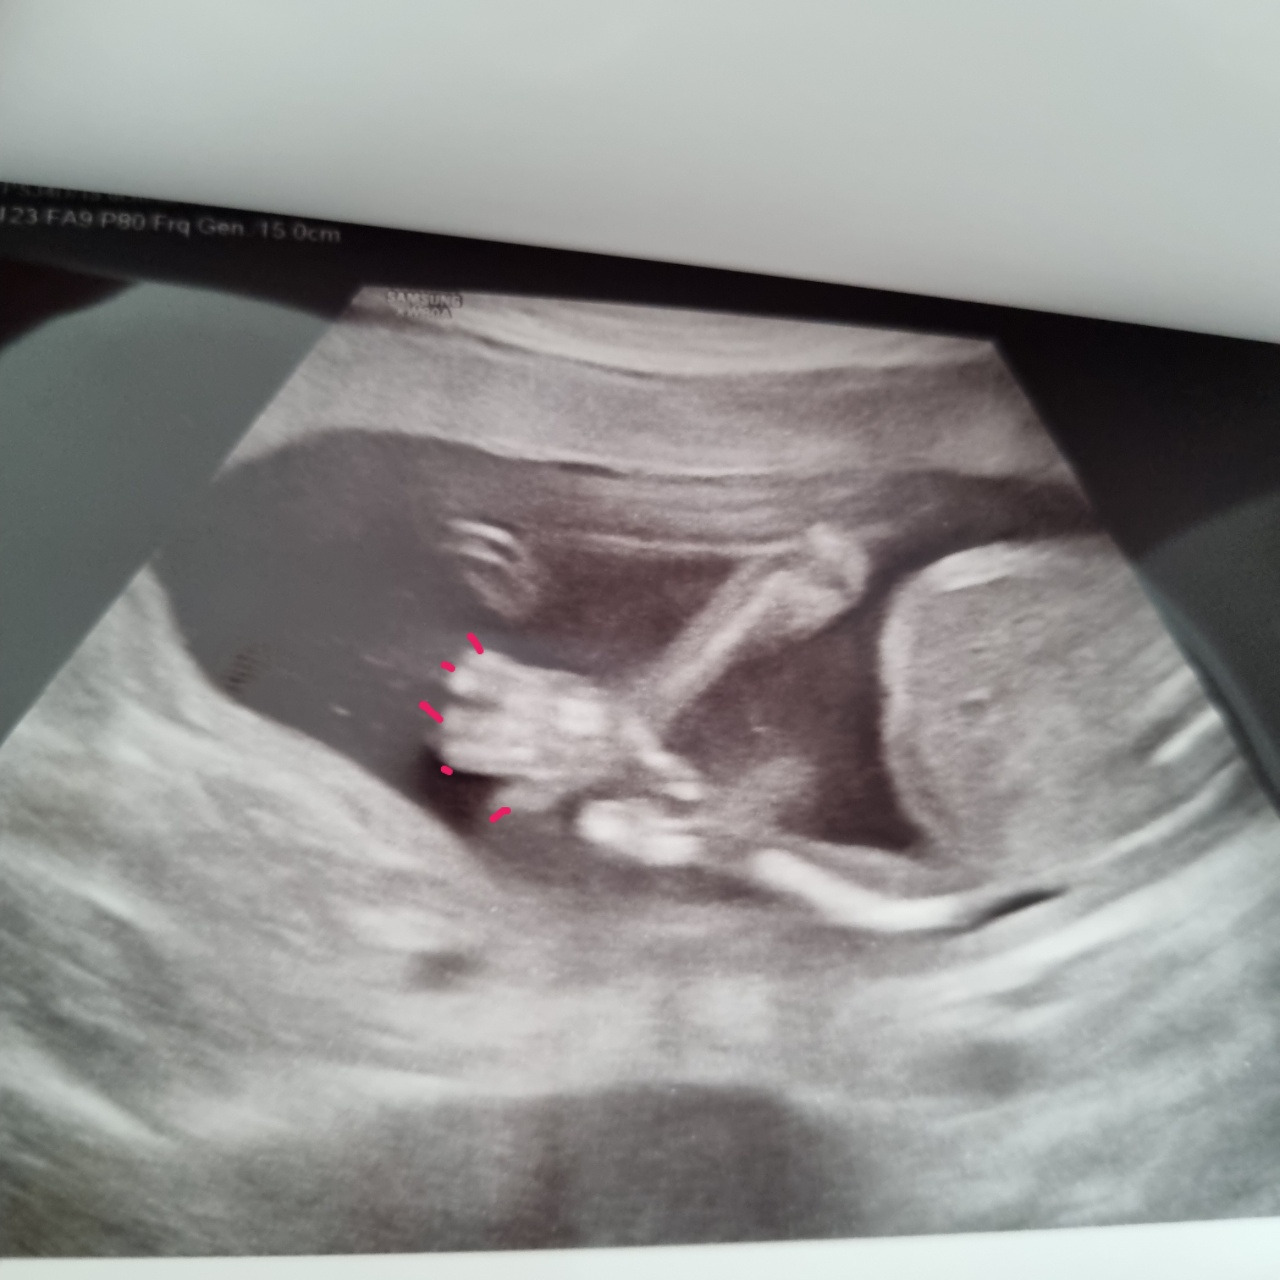

원래 다음 산부인과 검진일은 11월이었는데 아내는 아가가 너무 보고 싶다며 이번 주에 초음파를 보고 왔다. 손가락도 5개, 발가락도 5개 아주 예쁘게 잘 자라고 있다. 저 작은 손가락에는 지문도 생긴다고 한다. 이제 정말 디테일한 부분까지 같이 자라고 있는 셈이다. 아가는 저번 초음파 때에도 다리를 꼬고 있었는데, 이번에도 꼰 채로 놀고 있었다. 아무래도 다리 꼰 자세가 편한 모양이다.